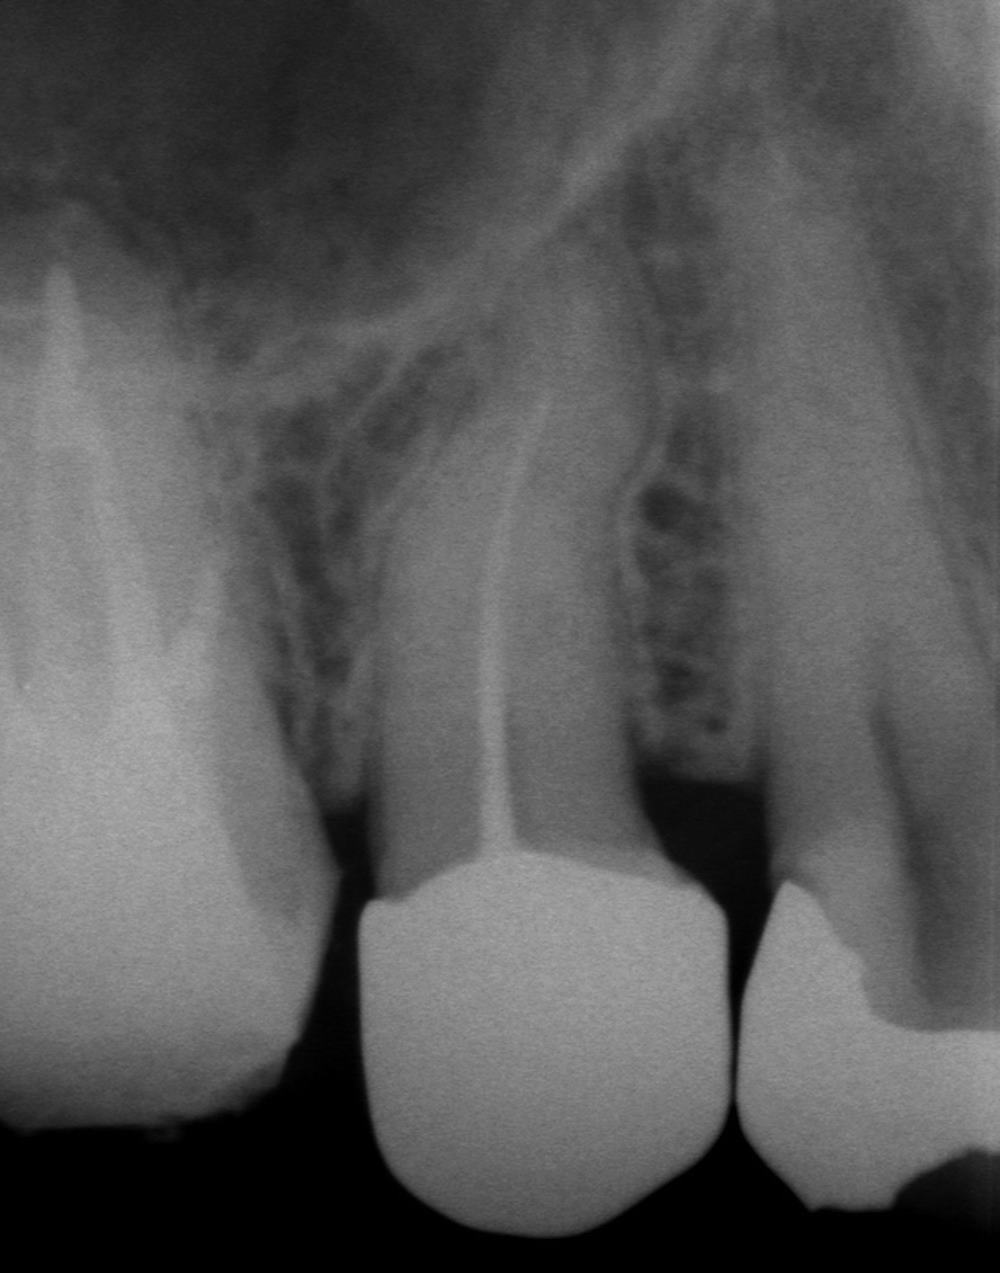

術前のレントゲン写真です。根管治療の質も悪いため、根管治療もやり直すことにわりました。

術直後のレントゲン写真です。レントゲン写真上では、問題なく根管充填できています。

術後3年後のレントゲン写真です。3年経っても、問題はまったく起こっていません。今後、なにかのトラブルが起こる可能性はありますが、今の段階では成功している、と言っても良いと思います。